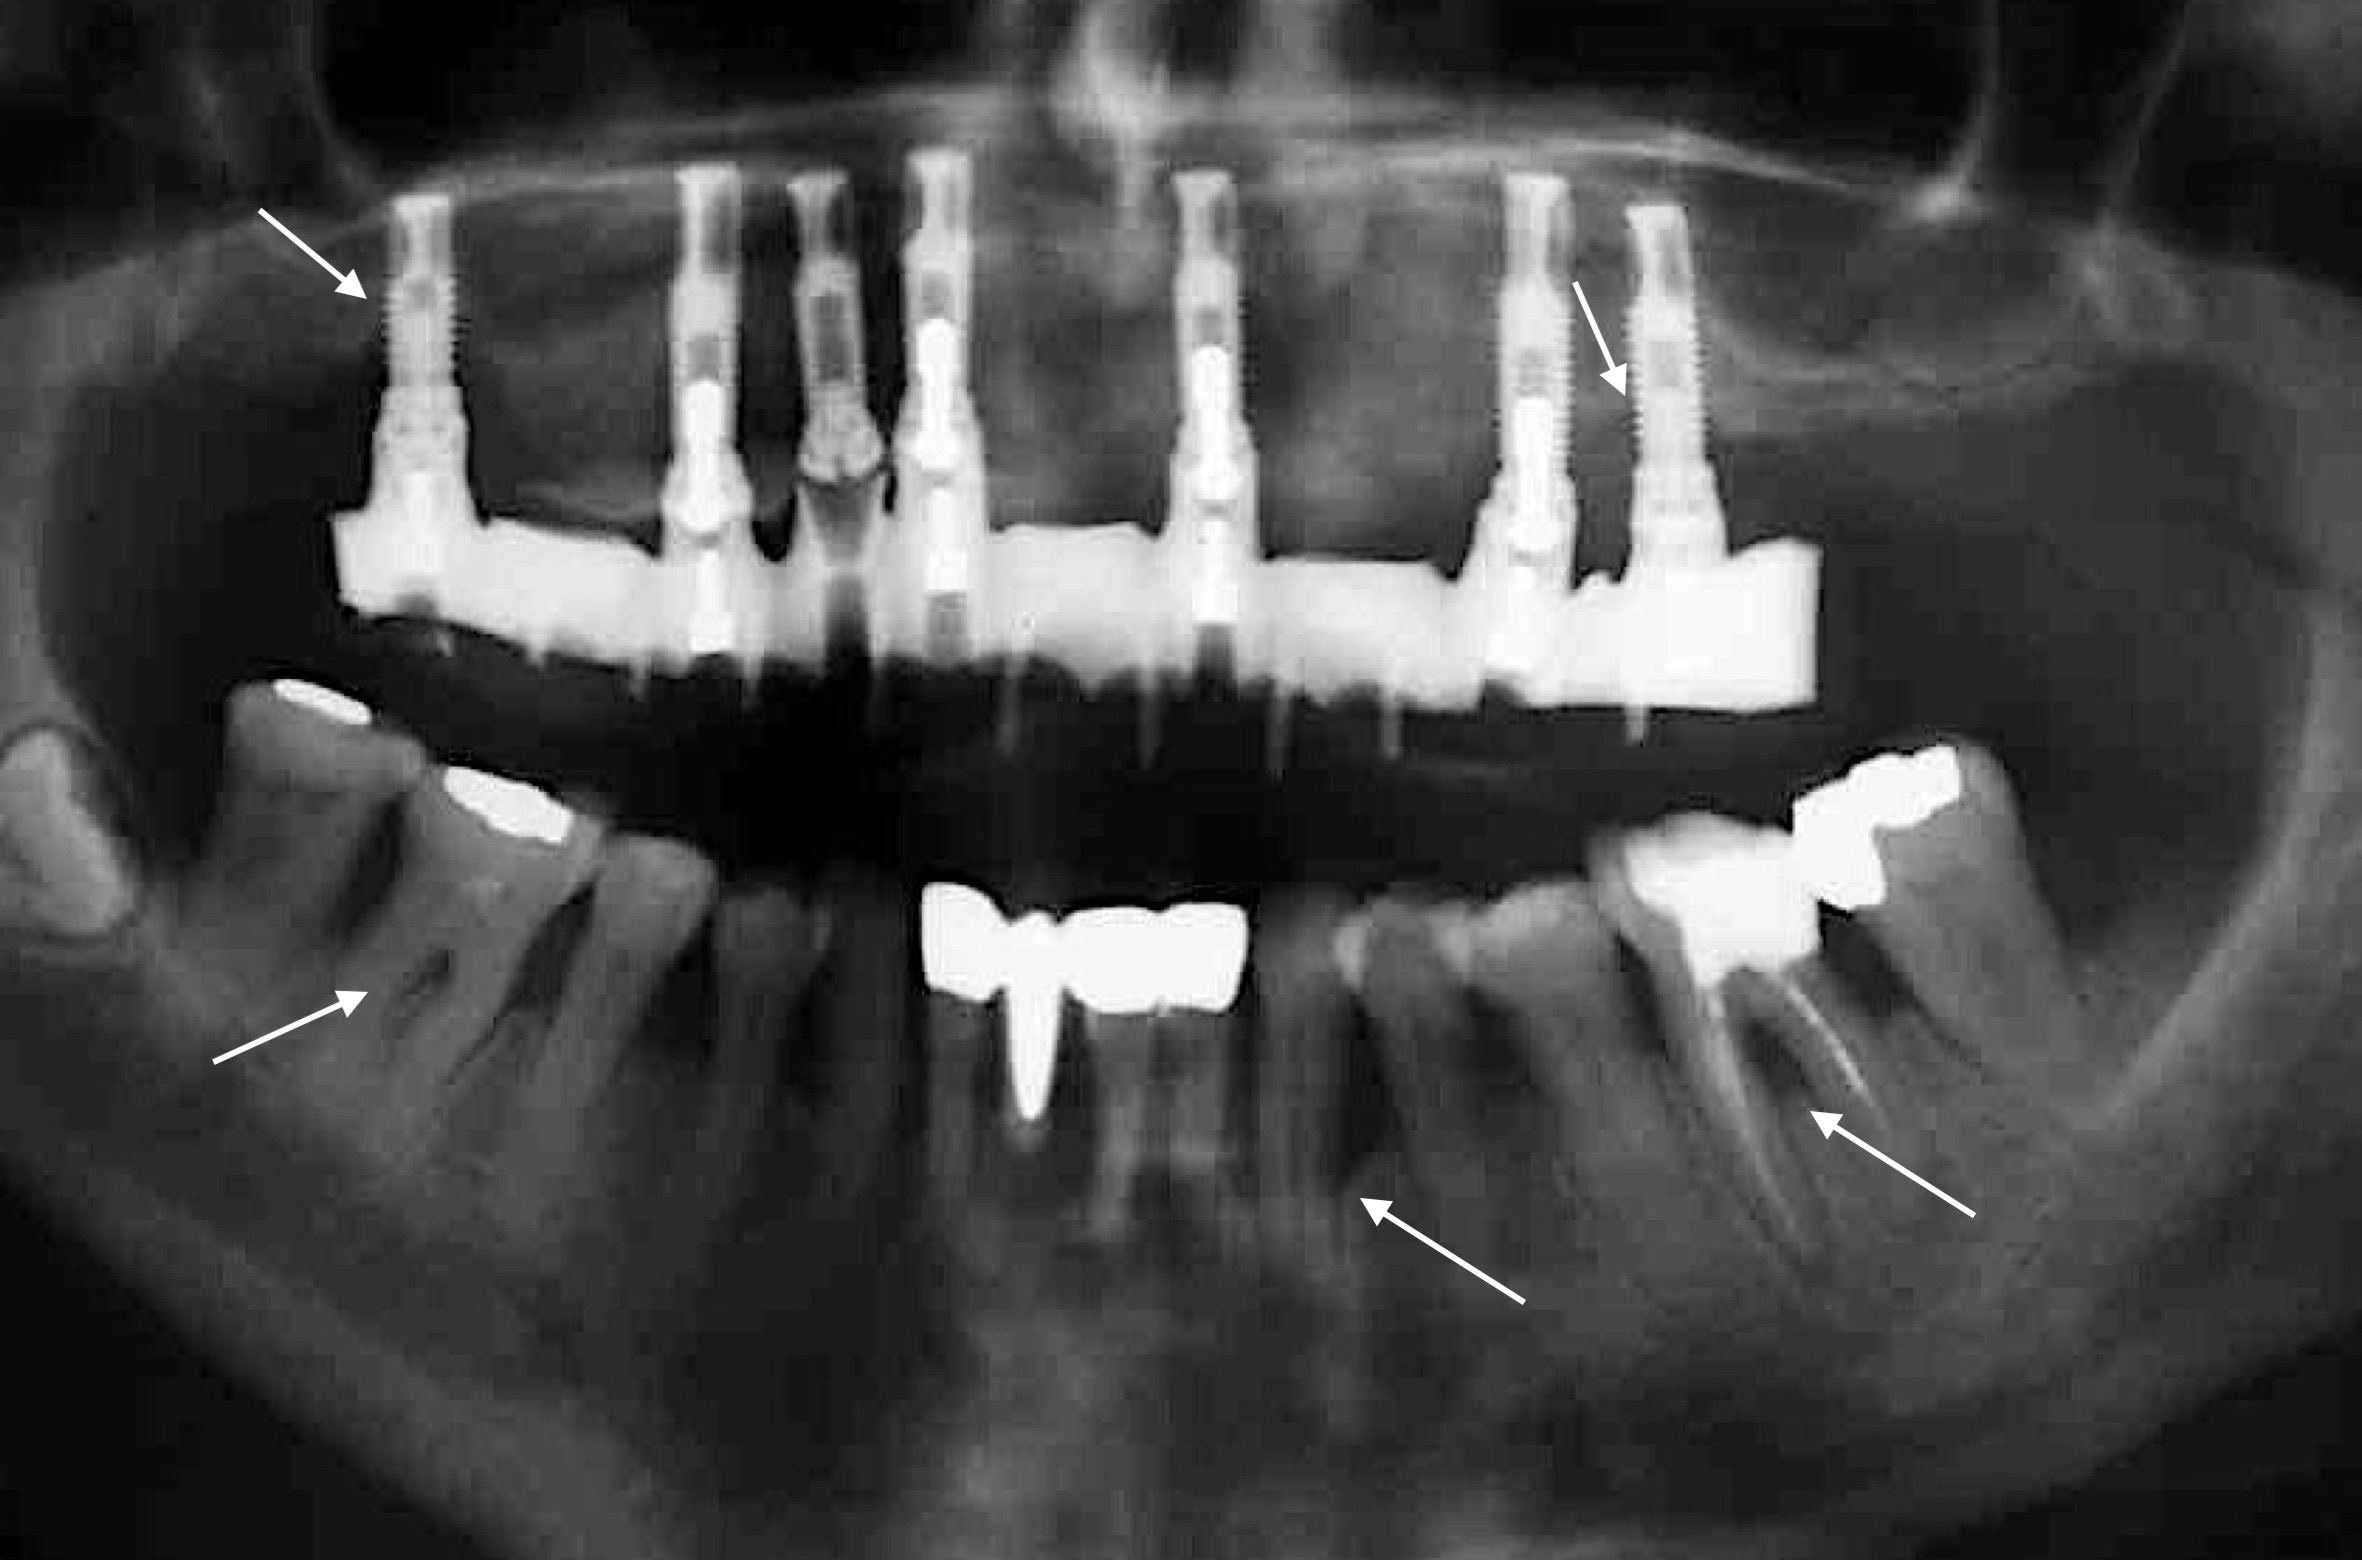

Zahlreiche Übersichtsarbeiten der letzten 10 Jahre belegen ein höheres Risiko eines Implantatmisserfolgs bei PatientInnen mit parodontaler Grunderkrankung (z.B.: Renvert & Persson 2009, Sousa et al. 2016, uvm.) und dieses Risiko scheint bei PatientInnen mit der Diagnose „generalisierte aggressive Parodontitis“ noch zusätzlich erhöht zu sein (Monje et al. 2016). Um diese Komplikation möglichst zu vermeiden, gilt es den/die Patienten/Patientin parodontal möglichst gut im Griff zu halten! Das bedeutet: 1) Die parodontale Therapie muss vor der Implantattherapie stattfinden; 2) Strikte Optimierung der Mundhygiene und vor allem gezielte Re-instruktion nach Eingliederung der Implantat-getragenen Versorgung; 3) Planung und Durchführung regelmäßiger Recallsitzungen um einerseits kein Rezidiv in Bezug auf die Parodontitis zu erleiden und andererseits peri-implantäre Erkrankungen frühzeitig zu erkennen; und 4) Rest-Sondierungstiefen nach der parodontalen Therapie möglichst vermeiden! Warum ist letzteres so wichtig? Eine Studie aus Australien (Cho-Yan Lee et al. 2012) hat sehr schön gezeigt, dass das Risiko eine Peri-implantitis zu entwickeln bei Parodontitis-PatientInnen mit Restsondierungstiefen (≥ 6mm Sondierungstiefe) im Vergleich zu Parodontitis-PatientInnen ohne Restsondierungstiefen und parodontal gesunden PatientInnen 4- bis 5-fach erhöht ist!

Nichtsdestotrotz sollte man nicht nur die negativen Aspekte sehen, denn man kann natürlich auch bei Parodontitis-PatientInnen eine hohe Implantatüberlebensrate von rund 92 % nach 10 Jahren erzielen (Zangrando et al. 2015)!